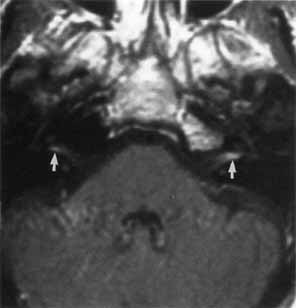

The facial paralysis associated with facial nerve neuromas usually has a gradual onset, but it may be more rapid, simulating idiopathic facial paralysis. Indeed, the pareses may fluctuate or may be associated with hemifacial spasm. In some cases, hearing loss precedes the onset of facial weakness, thereby simulating an acoustic neuroma.93 CT scan typically shows a uniformly enhancing mass in the fallopian canal. T2-weighted MRI images may show a hyperintense mass in the facial canal89 that enhances with gadolinium on T1-weighted images (Fig. 16). The ultimate diagnosis of facial neuroma requires surgical exploration and biopsy. Biopsy usually results in facial paralysis. This possibility should be discussed with the patient before surgery. Facial function recovery after resection of tumor and grafting, although never normal, may include restored tone, symmetry, and weak voluntary movement. The more facial function present before surgery, the better the results with grafting. This observation must be shared with the patient, because he or she might elect to wait until facial function is lost before consenting to surgical removal. When the tumor is located eccentrically, removal is possible with preservation of facial function.94

Fig. 16 Patient with facial neuroma. A. Coronal CT scan demonstrating enlarged stylomastoid foramen and facial nerve mass (arrow). B. Note size of canal in Figure A (black arrow) compared with normal sized canal (open arrow). C. Axial MRI scan showing an enhancing mass of tympanic segment (arrow). D. Coronal gadolinium-enhanced MRI section demonstrating same mass in mastoid segment (arrow).